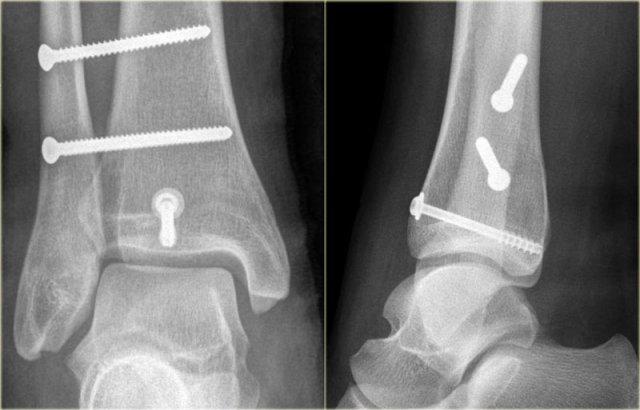

Trong phẫu thuật, cổ chân được xác định là không vững và vít cố định khớp chày mác đã được đặt vào.

Có chỉ định cố định gãy mắt cá sau vì mảnh gãy chiếm hơn 25% diện khớp của đầu dưới xương chày.